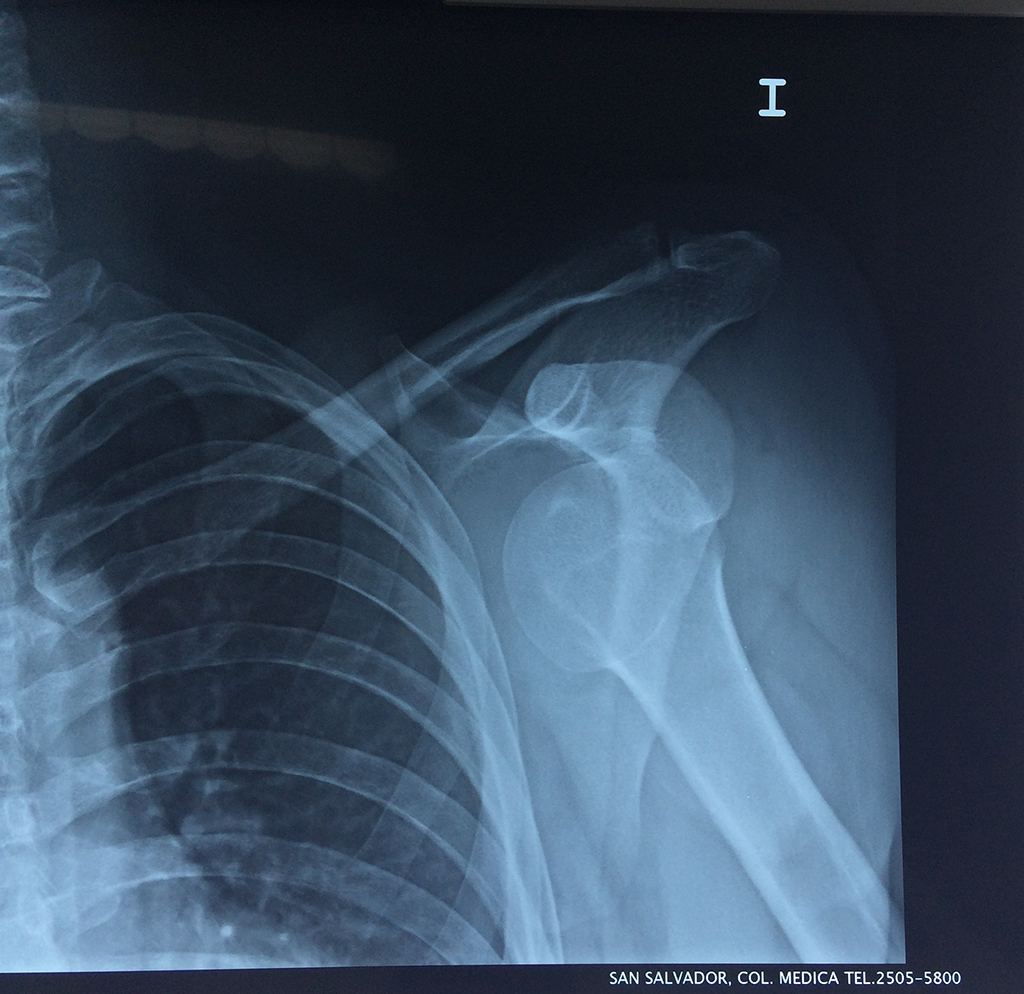

En anatomía humana, el hombro es la parte del cuerpo donde se une el brazo con el tronco. Está formado por la conjunción de los extremos de tres huesos: la clavícula, la escápula y el húmero; así como por músculos, ligamentos y tendones.

La principal articulación del hombro es la que une la cabeza del húmero con la escápula, recibe el nombre de articulación escapulohumeral y presenta dos superficies articulares, una de ellas corresponde a la cabeza del humero que tiene forma semiesférica y la otra es la cavidad glenoidea de la escápula, estas superficies están recubiertos por cartílago que permiten un movimiento suave e indoloro.